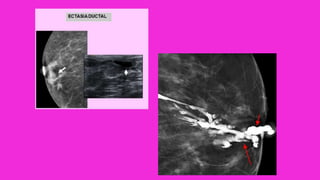

ECTASIA DUCTAL MAMARIA

• Este trastorno tiende a ocurrir en la quinta o la sexta

décadas de la vida, usualmente en mujeres multíparas.

• Las pacientes se presentan con una masa periaerolar

palpable poco definida, muchas veces asociada a

secreción blanca espesa por el pezón y en ocasiones a

retracción cutánea.

• El dolor y el eritema son infrecuentes.